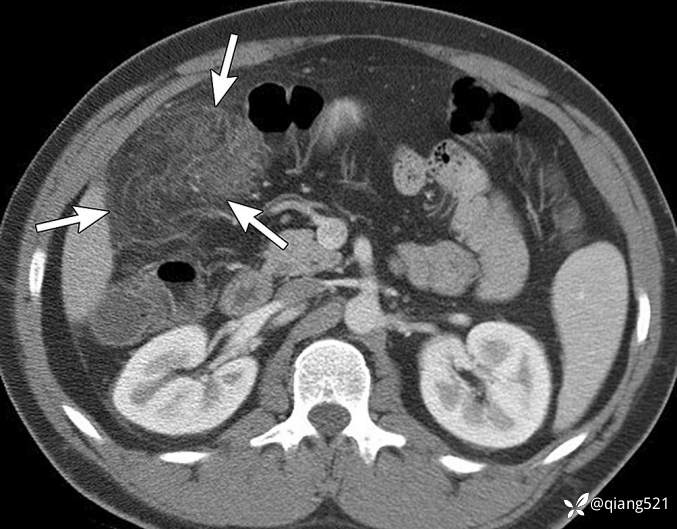

50岁男性,活检证实为炎性假瘤。CT显示右下腹有一个不均匀的肿块(箭头),右后肾旁间隙有一个软组织结节(粗箭头)。